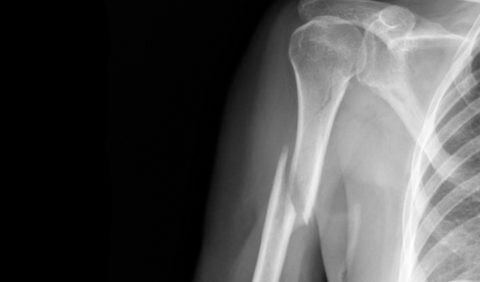

Рентгенологический снимок оскольчатого перелома головки плеча

В современной медицине редкими оказываются оскольчатый перелом шейки плеча или головки, что связано с их анатомическими особенностями. Если же все-таки одна из вышеуказанных травм имеет место, то на рентгеновском снимке наблюдается головка, что сдвинута или почти полностью оторвана.

Необходимо отметить, что наличие смещения нуждается также в применении остеосинтеза, который осуществляется во время хирургической операции. Данный вариант лечения перелома оскольчатого плеча считается одним из наиболее эффективных вариантов лечения среди всех предлагаемых. Контролировать процесс того, как срастаются кости плеча после перелома, врачу удается с помощью рентгеновских снимков.